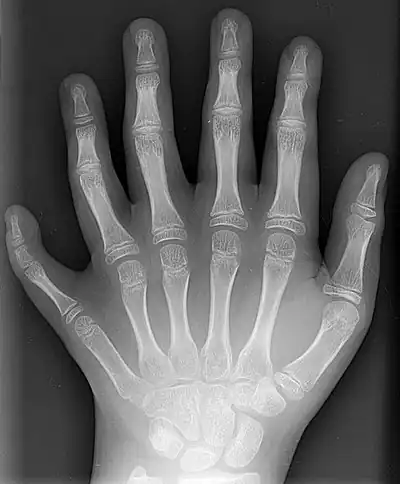

General images –